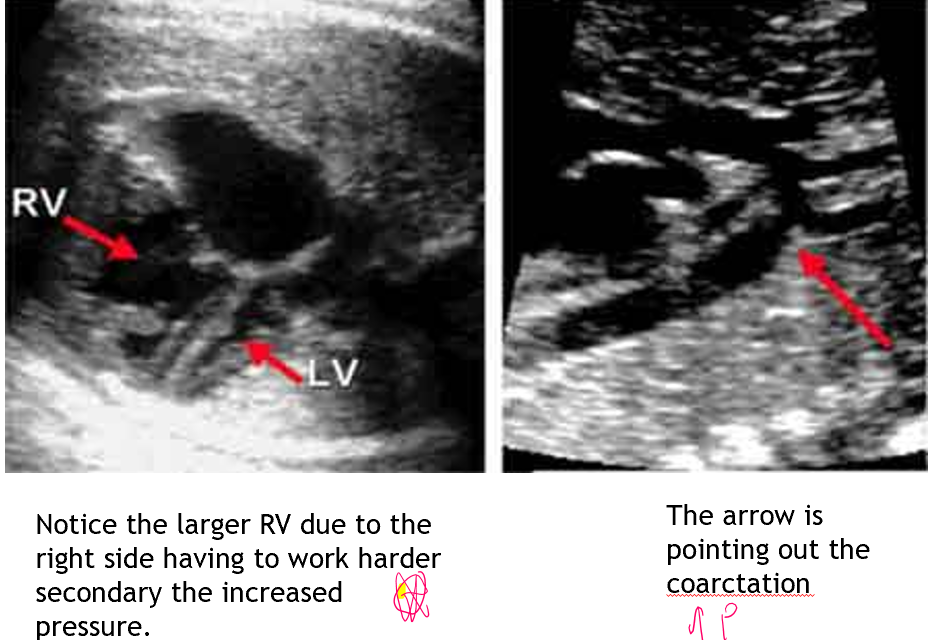

how can coarctation affect hemodynamics?

normally blood flows from right to left

narrowing of ao isthmus causes resistance for LV output

LV afterload increases and output decreases

distal to the narrowing may have lower pressure now than pulm art

RV output increases and pressure loaded

therefore blood may now go from ao to pa

what will happen in coarctation after the ductus arteriosus begins to constrict/close after birth?

increases LV pressure and afterload

LVH

increases LAP

increase in pulm venous pressure occurs leading to eventual RV dilation

prominent collaterals

BP differences of upper and lower extremities

more elevated in upper extremeties

how does the ao appear distal to the coarctation?

dilated